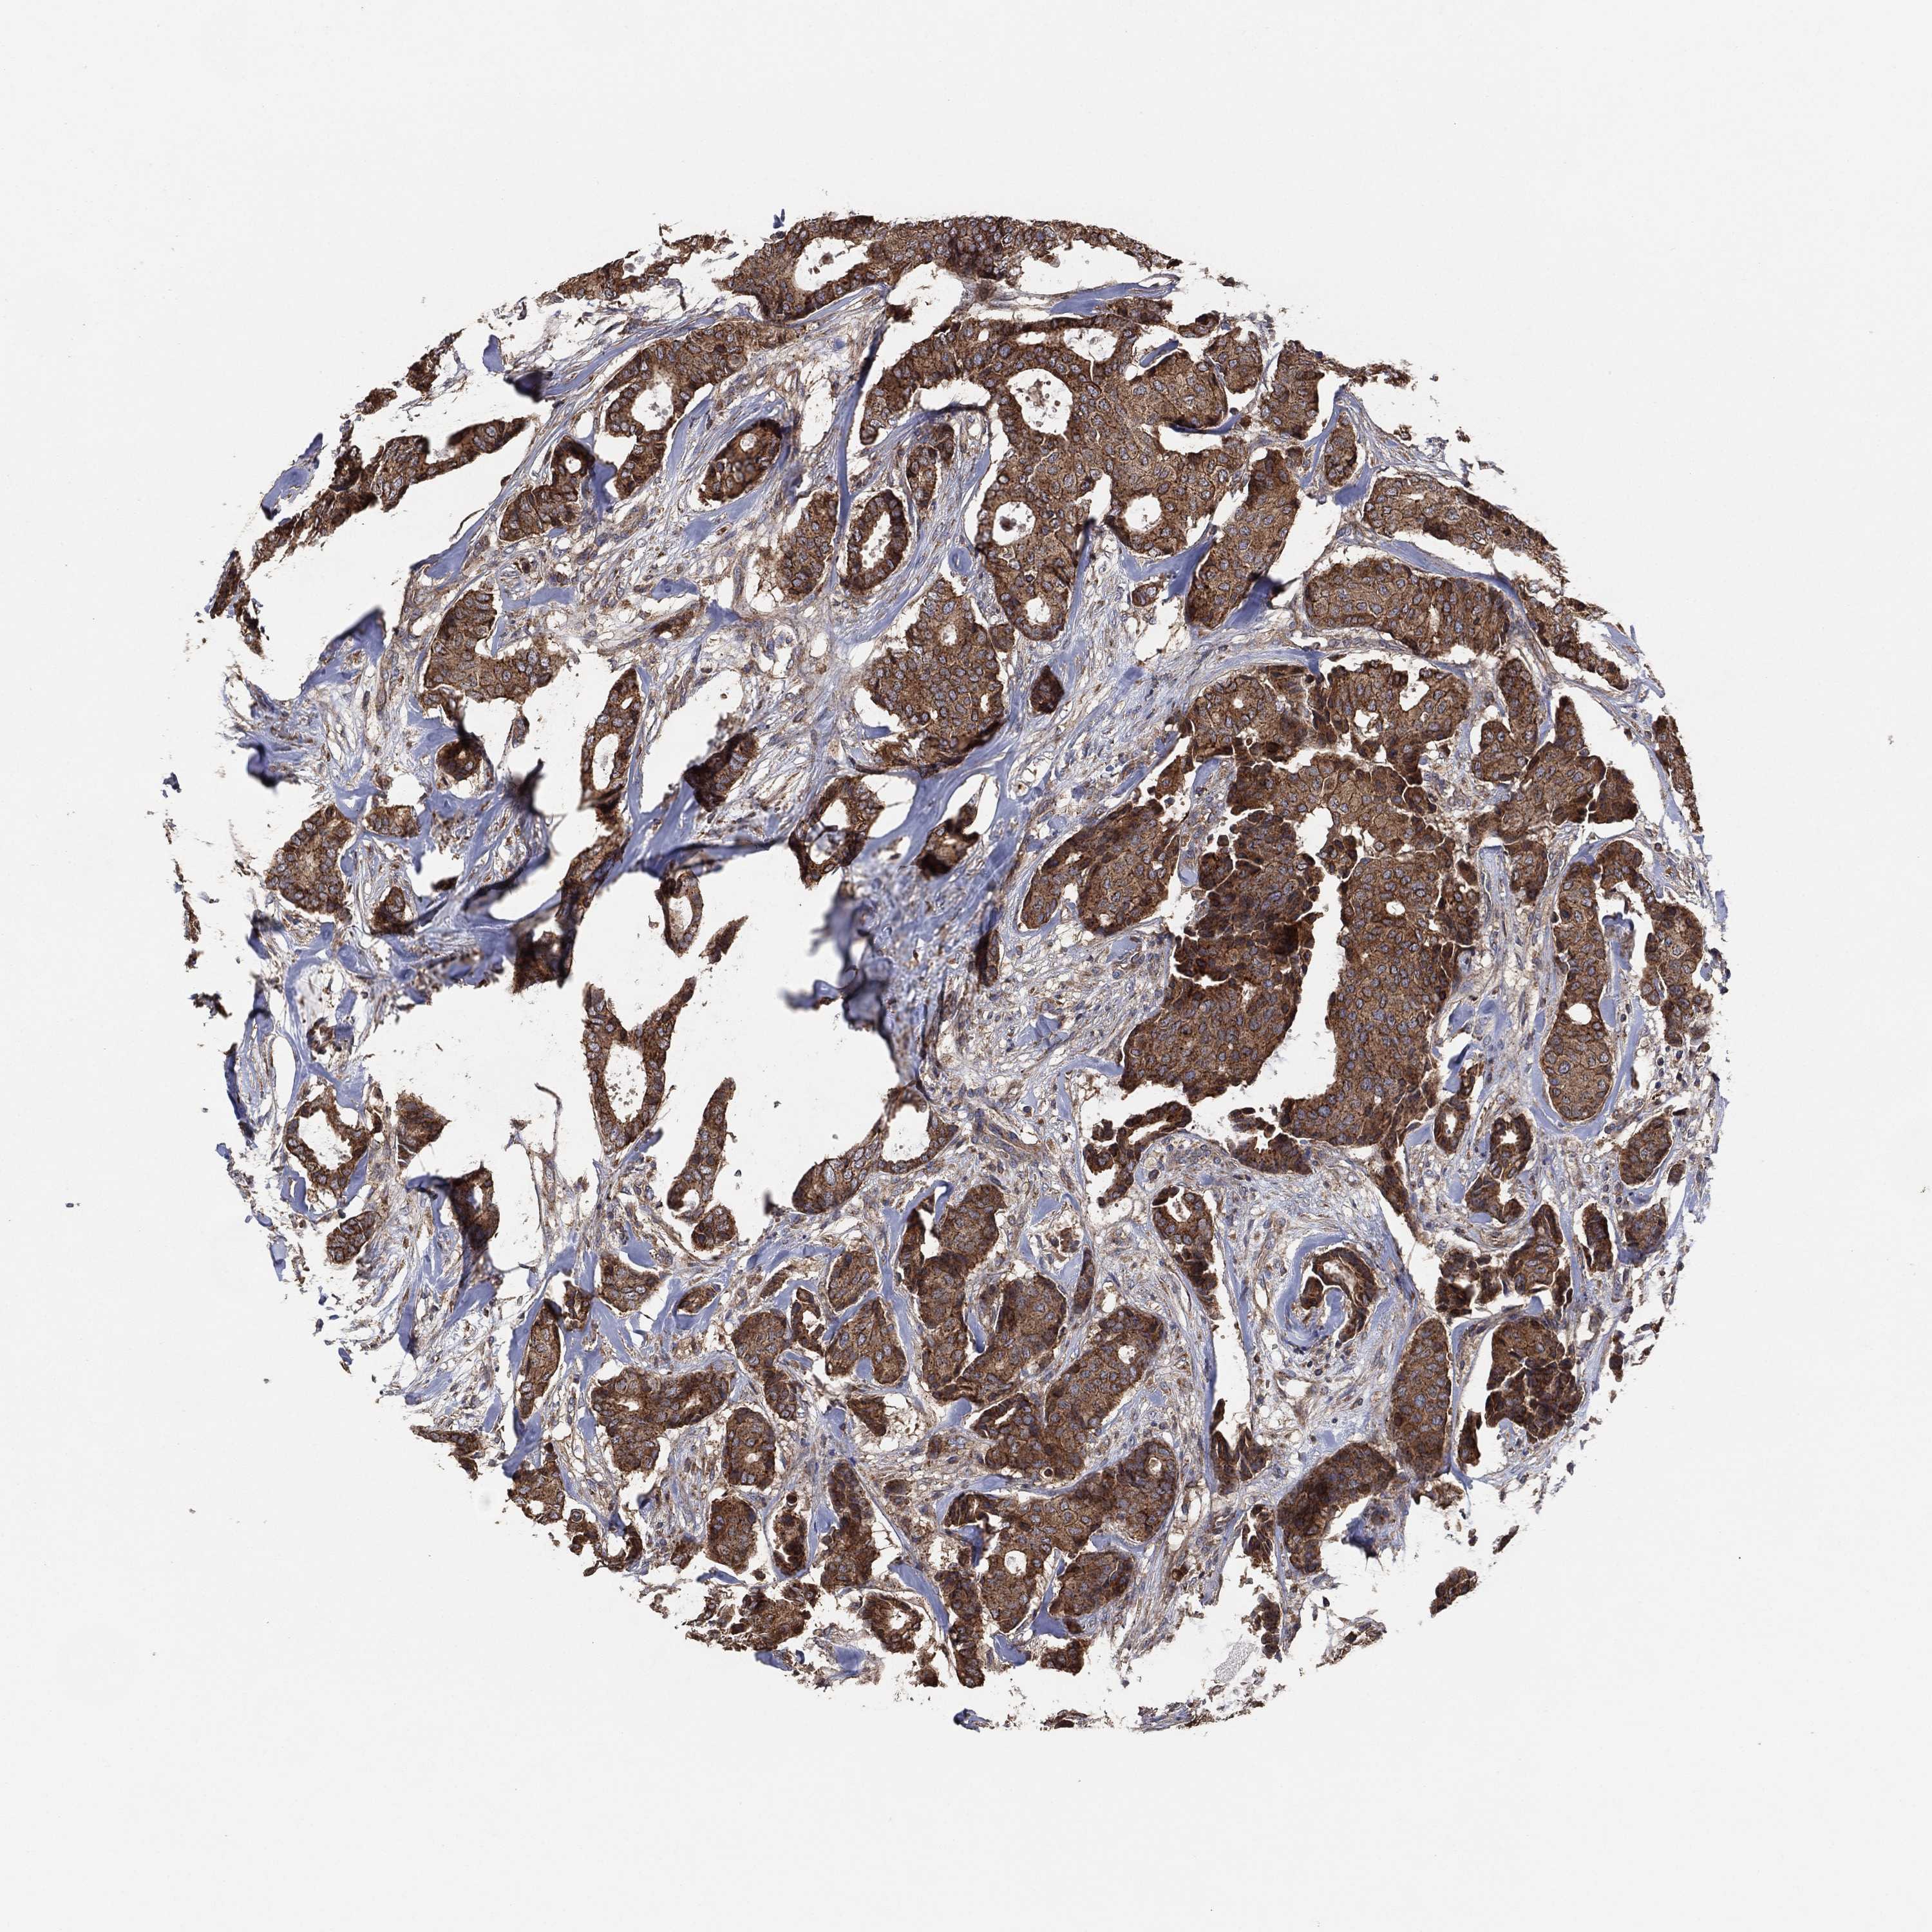

CANCER BREAST CANCER Show tissue menu

BRCA TCGA BRCA VALIDATION PROTEIN EXPRESSION